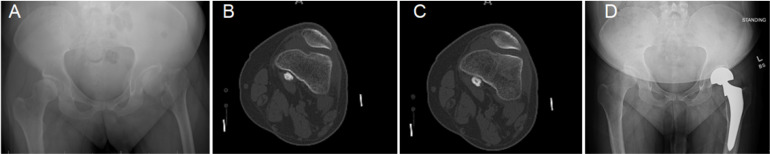

Purpose: There is limited evidence regarding the outcomes of hip hemiarthroplasty (HA) following trauma in individuals living with Down syndrome (DS). This study aims to summarize the outcomes of hip HA in a series of individuals living with DS following femoral neck fractures.

Materials and methods: This retrospective study includes five cases of hip HA in four individuals with DS and displaced femoral neck fractures. Subjects (four males) had a mean age of 49.3 years (range, 26.1-59.7 years) at the time of surgery. All subjects presented with hip pain, loss of weight-bearing ability, and decreased activity level as reported by the subject caregivers. In all cases, the precise time of injury was not known.

Results: After a mean follow-up of 15.2 months, all subjects had returned to the pre-injury activity level without any recorded complications. One individual died 32 months after surgery for unrelated causes; the remaining subjects are alive and ambulating without pain at a mean of 24.2 months since the surgery.

Conclusion: When treating femoral neck fractures in those living with DS, careful history taking should be performed as regards the timing of trauma and the individual's functional status. Hip HA seems a viable treatment option for those living with DS if a proper surgical procedure is utilized.